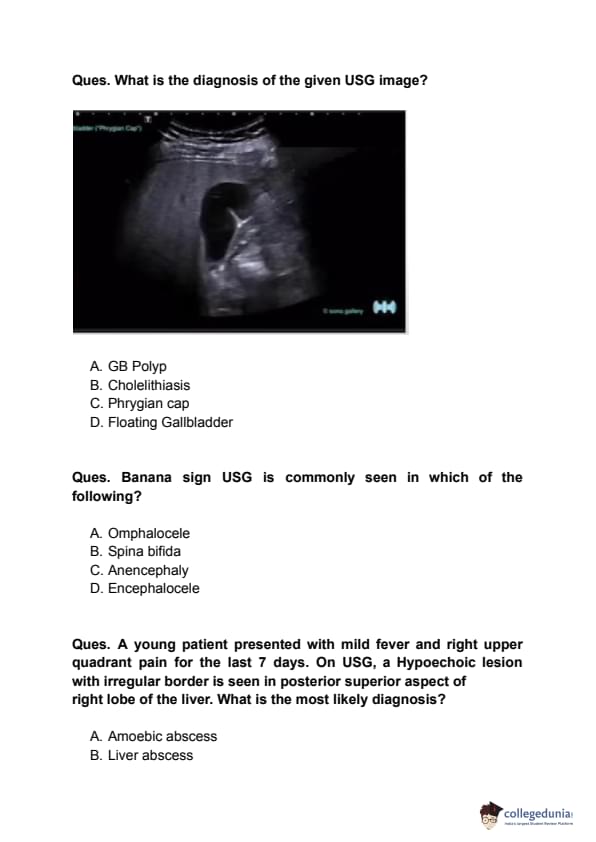

INI CET 2023 Question paper with Solutions PDF for May 7 exam is available here for download. INI CET 2023 question paper pdf comprises 200 multiple-choice questions to be attempted in 3 hours. The question paper of INI CET 2023 is for a total of 200 marks and there is a negative marking of 33.33% for each incorrect answer.